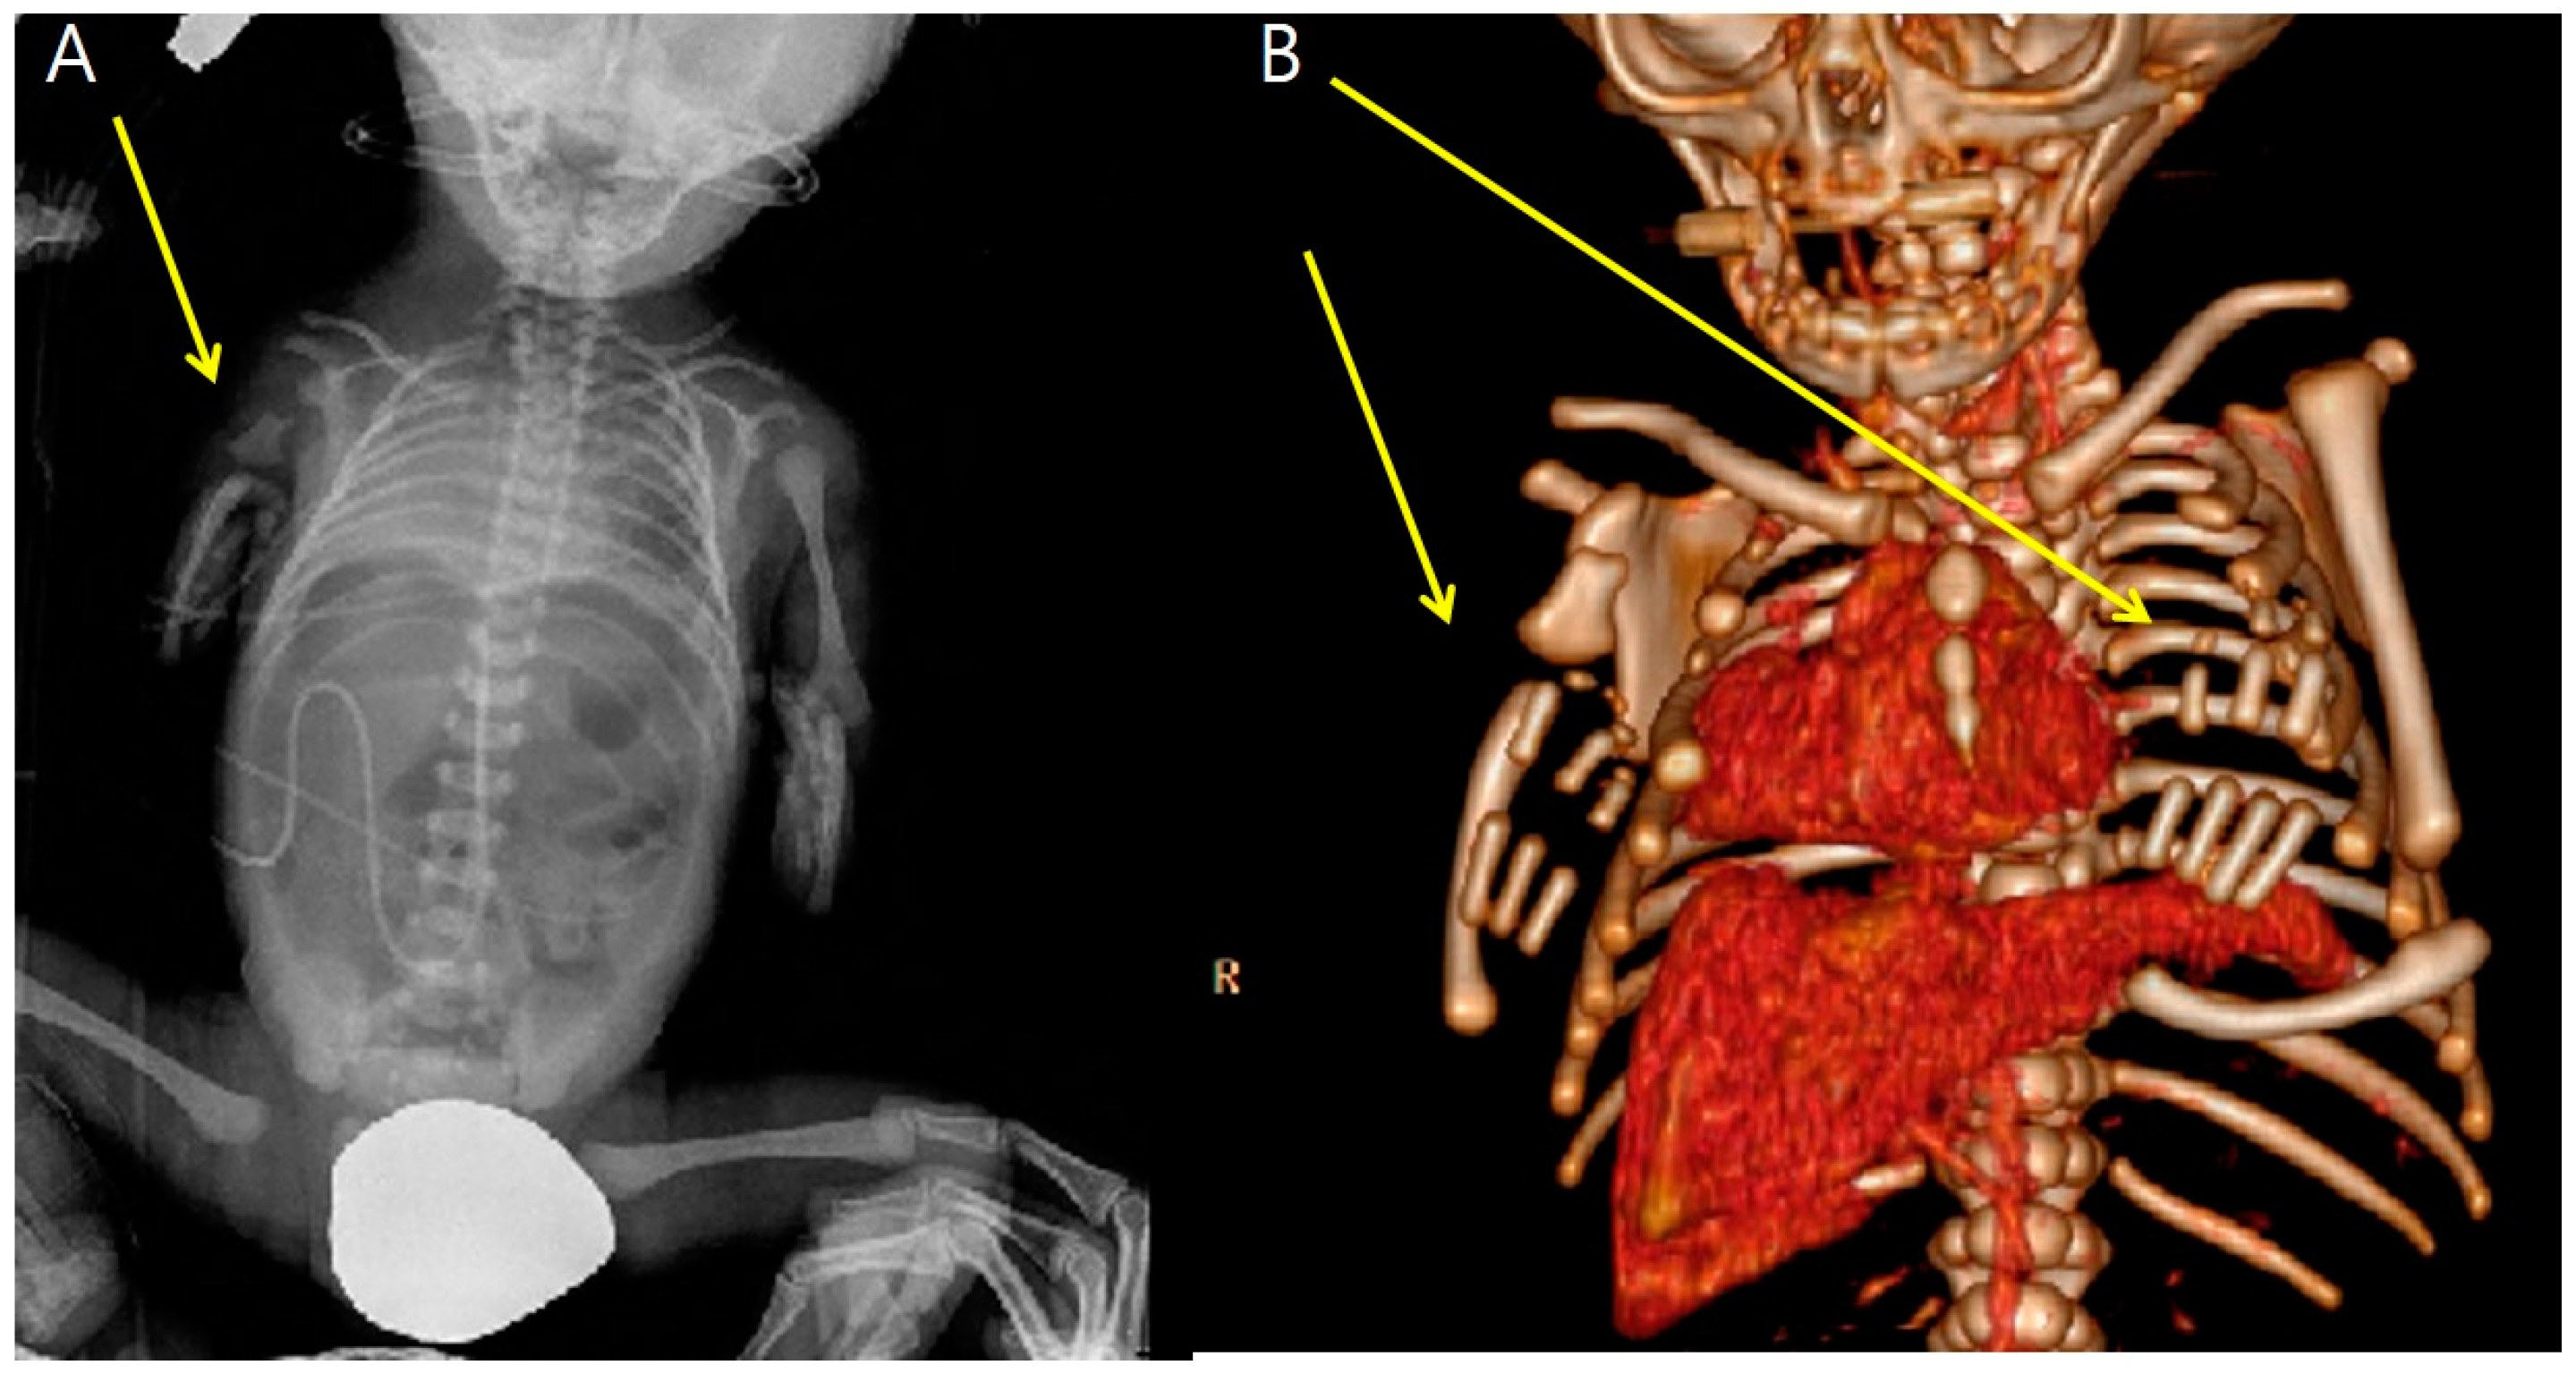

At 34 + 0 weeks gestation, an emergency cesarean delivery was performed because of relapsed preterm labor. The first baby was a male with VACTERL-H association, weighing 1390 g, and the second baby was a healthy female, weighing 1890 g. The Apgar scores at 1 and 5 min were 6 and 8 in the first twin baby and 5 and 8 in the second twin baby. The first twin had multiple anomalies diagnosed prenatally. Related imaging studies were performed, including an infantogram and 3D CT (Figure 8, Figure 9, Figure 10, Figure 11 and Figure 12). A cardiacangio 3D CT revealed dextrocardia of embryonic arrest with pulmonary hypoplasia and a tracheoesophageal fistula with a right bronchus (Figure 8). The infantogram and 3D CT showed upper-limb agenesis, which aligned with the prenatal diagnosis, including aplasia of the right proximal humerus, radial hypoplasia, and hypoplastic thumb (Figure 9, Figure 10 and Figure 11). The first twin baby also had an imperforate anus and colon dilatation (Figure 12). Neonatal echocardiography showed dextrocardia with right atrial enlargement and an interrupted inferior vena cava without major congenital cardiac abnormalities. The findings from postnatal imaging supported the prenatal diagnosis of a VACTERL-H association. On his fifth day of life, the twin baby with the VACTERL-H association died.

Figure 8. 3D cardiac angio computed tomography of fetus A. (A) Dextrocardia of embryonic arrest with pulmonary hypoplasia from posterior to anterior coronal view. (B) Dextrocardia of embryonic arrest with pulmonary hypoplasia from anterior to posterior coronal view. (C) Tracheoesophageal fistula with right bronchus (white arrow). (D) Tracheoesophageal fistula with right bronchus (yellow arrow).